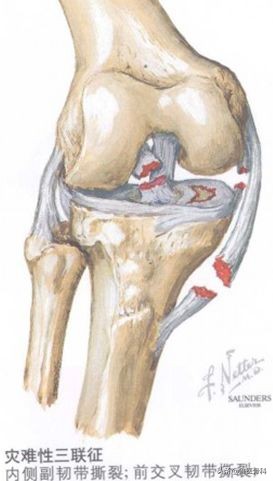

3)内侧副韧带断裂多合并前交叉韧带、内侧半月板损伤,称为“膝关节损伤三联征”。